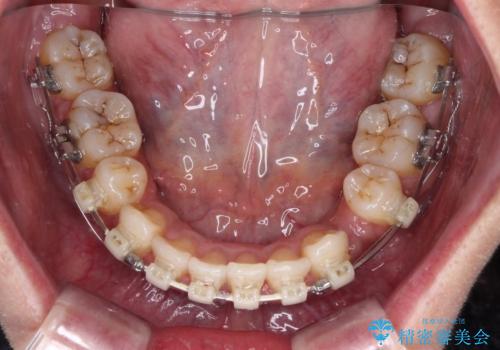

- 審美装置

- 2年6ヶ月

- 10-30回

- 八重歯と上下前歯のでこぼこを気にして来院された患者様です。

上下前歯部叢生のスペース獲得のため、上下顎左右小臼歯各1歯(計4本)を抜歯して、ワイヤー装置にて矯正治療を行うこととしました。

上下の正中位置が大きくずれていたため、上下正中が合わないまま終了することが予想されましたが、思っていた以上にスムーズに歯が移動し、満足いただける仕上がりとなりました。